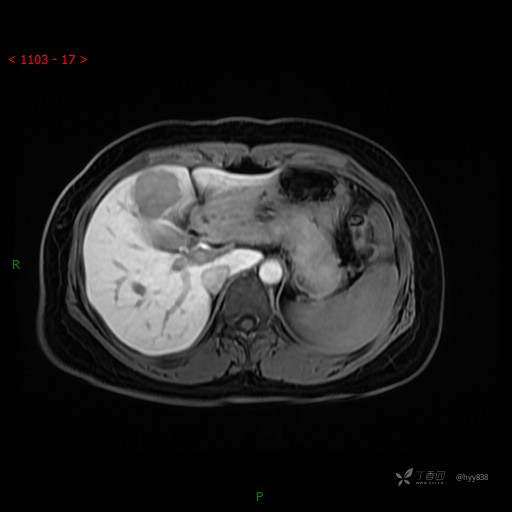

动态增强(动脉早期、动脉晚期、门脉期)

延迟肝胆期